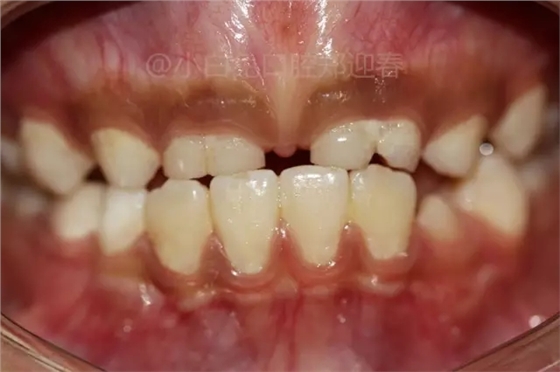

患兒,10歲,因上前牙未替換來(lái)診,查體:輕度反合,51和52、61和62均融合,且存在間隙約4mm,全面曲面斷層片顯示:11、21未萌,52、51、61、62牙根均有不同程度的生理性吸收。